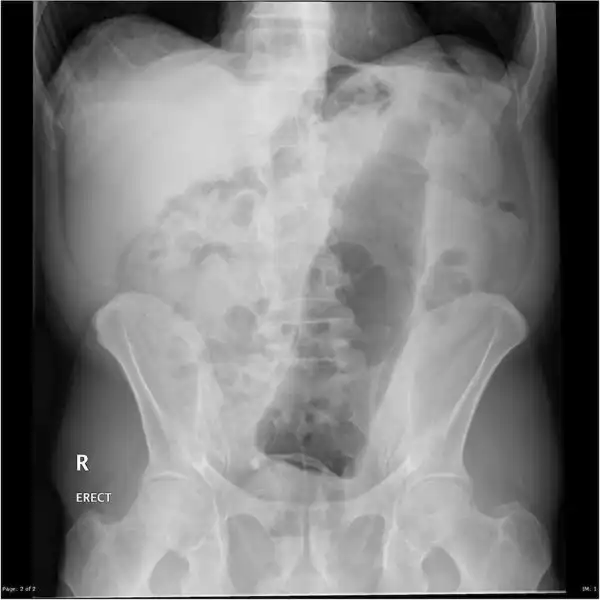

Врачебные находки в интимных местах

Или как впихнуть невпихуемое :lol:

Из личной коллекции. Извлек из очень озорного дедушки.

Затейники, не дают скучать хирургам

Самое интересное, что со слов пациентов, будучи совсем голыми поскользнулся и упал аккурат причинным местом на указанный предмет)))))

Это просто потрясающее-е-е-е-е!!! о_О Вот до чего доводит жажда острых ощущений! А еще говорят - все дороги ведут в Рим... нет уж, по крайней мере некоторые ведут прямиком к хирургу. Или даже в паталогоанатомический музей. Если не повезет.